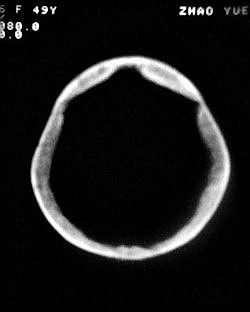

患者/49y/ 女/4年前有脑梗, 现因右侧肢体无力来院做ct扫描 ! 老师们看看这骨头有事吗?钙化点是什么原因呀??

1.颅骨对称性、形态规整性增厚,应属发育异常。四叠体池左后侧单发点状钙化,无其他阳性表现,多属正常,不需要过多关注。

2.双侧基底节区域多发性梗塞灶。

2、颅骨形态规整性的增厚,密度增高,有无骨髓方面的疾病,建议骨髓穿刺。

2.颅骨内外板广泛性增厚,板障狭窄甚至消失,双侧对称。无明显相应临床症状。考虑“泛发性骨皮质增厚症”。可进一步检查下颌骨及管状骨骨干。(下颌骨骨小梁增多、密集,密度增高亦为本病特点,管状骨骨干皮质向内增厚引起骨皮质厚度增加,骨密度增浓、髓腔狭窄但不消失,骨干周径较少增加)。与石骨症鉴别,后者很少影响颅盖骨和下颌骨,管状骨改变主要累及干骺端和骨骺,而骨干皮质较少增厚,椎体和髂骨翼有特征性表现。

“泛发性骨皮质增厚症,又称骨内膜增生症(endosteal hyperostosis):分为常染色体隐性遗传性疾病(van buchem)和常染色体显性遗传性骨硬化症(worth病)。后者更少见,亦较轻。两者的病理上均为骨内膜 成熟的板状新生骨形成,髓腔变窄。颅骨、颅底骨 、下颌骨,肋骨、四肢骨及骨盆骨、脊柱均可见骨内膜增生,髓腔变窄或消失,但骨外径不加大,骨骺不累及。”

本例的确应该这个病。建议楼主检查病人其他部位有无类似表现,以便确诊。